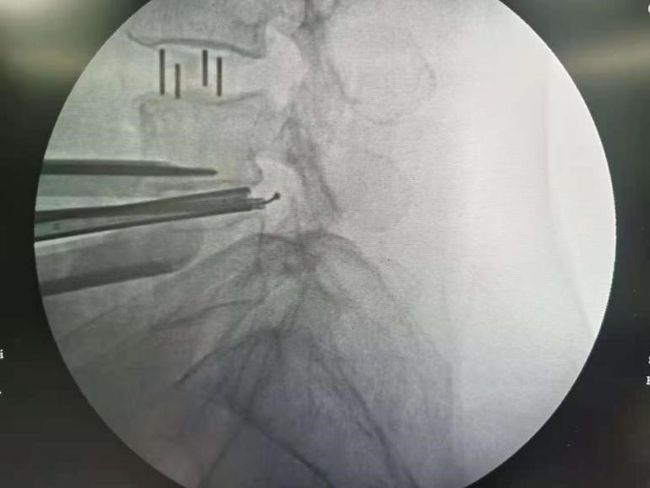

进一步完善术前检查后,余将明副主任医师亲自主刀,手术2小时左右,手术顺利,术后疼痛消失,患者恢复良好,非常满意。

OLIF手术

椎间隙撑开后达到间接减压的目的

OLIF微创手术是目前流行的一种微创椎间融合手术,通过撑开椎间隙达到间接减压的目的。手术从腰部斜前侧方入路,从自然间隙到达腰椎,椎间处理后椎间隙撑开,做一个滑脱的复位,然后再根据患者情况I期或II期后路置入钉棒固定。

本病例患者L3/4存在腰椎滑脱、椎间隙高度丢失;但L4/5椎间隙高度丢失不明显,所以选择了L3/4、L4/5两个节段的OLIF同是进行L4/5的内镜手术(OLIF+内镜),充分的结合了两种术式的优缺点,是间接减压与直接减压的完美结合。所以对于严重的椎管狭窄或滑脱也是可以采用微创的方式来解决的。目前国内开展此类微创手术鲜有报道。